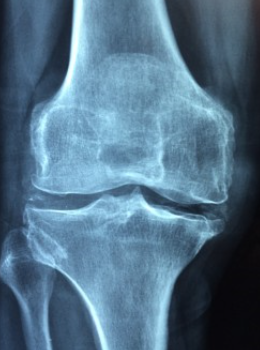

무릎 통증

무릎 통증이라고 생각하면 보통 40~50대 이상 부터 쉽게 통증이 많이 생긴다고 생각합니다. 나이가 먹고 노화에 따라 생기는 퇴행성이 가장 큰 원인이긴 하지만, 다른 원인에 의해서도 무릎 통증이 생깁니다.